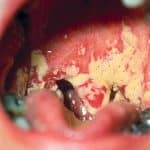

Eingerissene Mundwinkel - Behandlung und Diagnose vom Online-Hautarzt erhalten